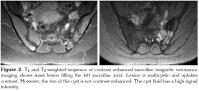

There were no abnormal findings of the lumbar spine on magnetic resonance imaging (MRI) (Figure 1). Contrast enhanced sacroiliac MRI revealed lobulated, multivesicular cystic lesions, which originated from the second sacral vertebra, extending to the sacral ala and iliac wing at the third sacral level, which also filled the sacroiliac joint. Vesicular lesions in the sacroiliac joint and piriform muscles showed increased contrast uptake (Figure 2). Given the patient's medical history, bone hydatid disease and other cystic bone lesions were included in differential diagnosis.

Furthermore, MRI usually helps to define features of the cyst except calcifications.[4] Hydatid cyst appears as well formed, thin-walled and spherical lesions on MRI.[10] The fluid of the cyst is isointense with cerebrospinal fluid both on T1 and T2-weighted images and the wall of the cyst appears as a low signal intensity rim. In defining the wall of the cyst, T2-weighted images are superior to T1-weighted images. Fluid has a high signal intensity and, in contrast, the wall of the cyst has a low signal intensity on T2-weighted images.[1] After intravenous contrast agent administration, the rim of the cyst shows no uptake. Calcification of the cysts wall is a very rare entity.[11] Computed tomography images resemble T1-weighted MRI images. Magnetic resonance imaging of our patient revealed characteristics of hydatid cyst. Regular, thin-walled cyst and pericystic contrast uptake was determined. Chronic osteomyelitis, fibrous dysplasia of bone osteosarcoma, benign cystic lesions of the bone, brown tumor (hyperparathyroidism), and neoplastic lesions all should be included in the differential diagnosis.[12,13] Localization of lesions is also important. Although our patient did not present with inflammatory back pain, she had a presumptive diagnosis of AS and was medically treated for two years. This caused a delay in the diagnosis and unnecessary use of medication. Hence, atypical presentation of hip or low back pain and its irresponsiveness to anti-inflammatory medication warrants further investigation.